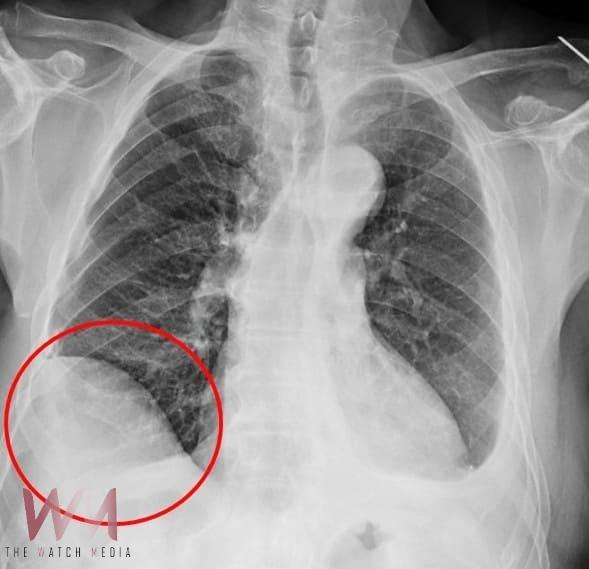

(觀傳媒中彰投新聞)【記者廖妙茜/台中報導】75歲吳先生因肝臟細胞癌在仁愛長庚合作聯盟醫院(大里仁愛醫院)接受治療,期間發現右下肺有一顆約1.2公分新發現的腫瘤,因疑似肺癌故轉介到胸腔及心臟血管外科廖啟耀主任門診,經醫療團隊和家屬討論後決定做手術切除該腫瘤。由於病人過去有車禍導致橫隔膜受傷的病史,所以讓手術預期難度相對提高,經採用達文西機器人手術系統執行肺節切除手術,並且順利地於術後第三天出院返家休養。

廖啟耀主任表示,雖然肺臟腫瘤手術在台灣十分普及且發達,但是有些病人的情況會使醫師預期手術難度提高,其中以過去有過外傷經歷、曾經接受過胸腔手術、肺臟腫瘤接受過放射性治療的病人最為常見,這類病人常見的手術困難度為解剖構造的改變,常因為胸腔發炎反應的影響,讓肺臟與周遭肋膜產生沾黏,同時血管的方向也更難分辨,對執行手術醫師而言是一項困難的挑戰。